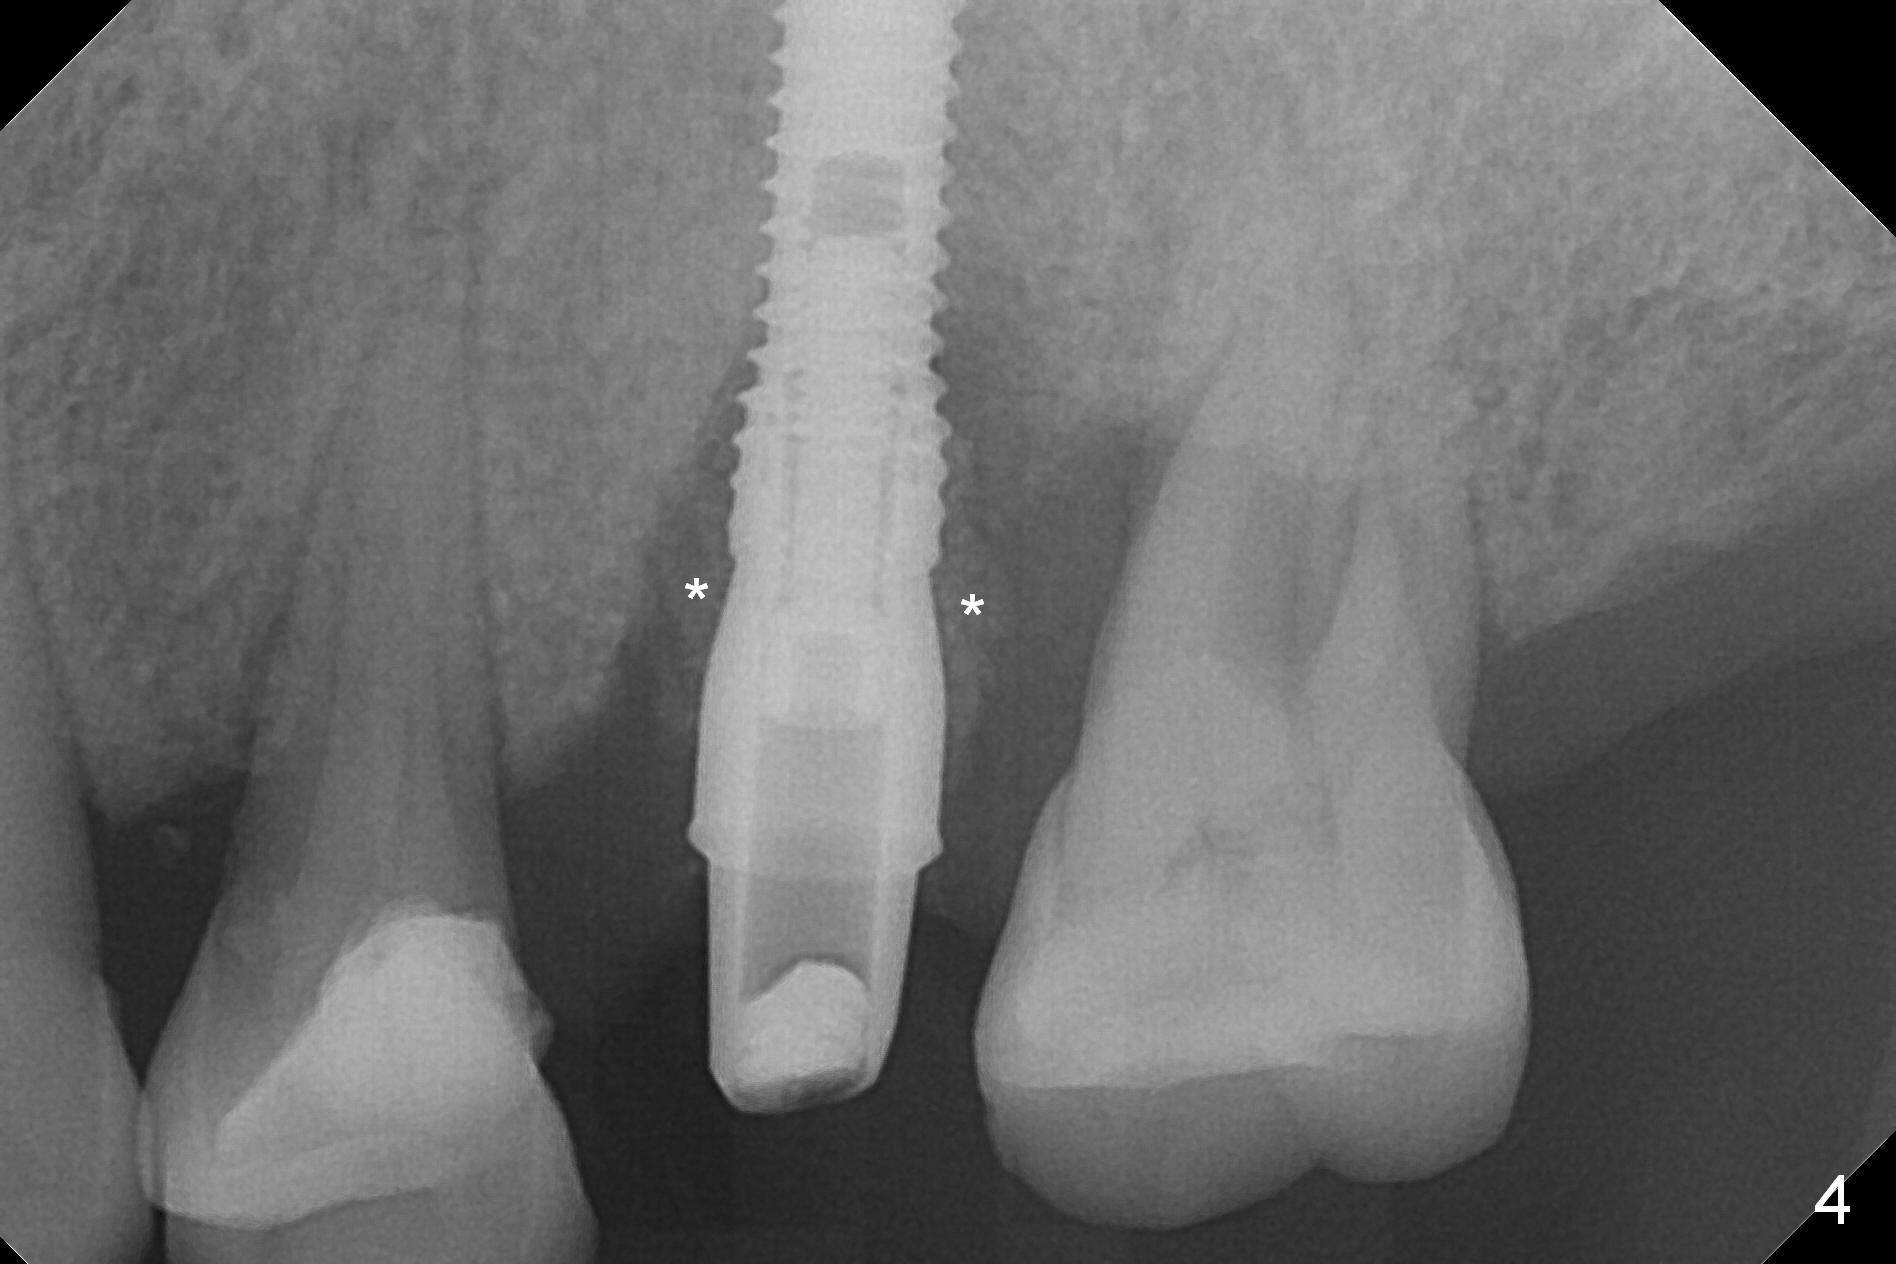

Initial osteotomy depth is 18 mm (Fig.1 green line) with 9 mm in the native bone (red line). The bone density feels to be low. There is at least 2 more mm bone apically (pink line). The depth is increased by 2 mm so that when a 3.8x15 mm implant is placed, there is 10-11 mm implant/bone contact (Fig.2 red line). There is large bony defect (Fig.3 *), which is bone grafted (Fig.4 *). Finally a longer abutment is placed (4.5x5.5(5) in Fig.4 vs. 4.5x4(5) in Fig.2,3). The 5 mm cuff does not look too long buccally (Fig.5) or palatally (Fig.6). To prevent postop buccal gingival overgrowth (2), the buccal margin of an immediate provisional is subgingival (Fig.7-9 *). Bone density between #13 and 14 appears to increase 3 months postop (Fig.10). The implant seems to be equi-crestal (Fig.11 ^). There seems to be more bone growth (i.e., decreasing gap) 6 months postop (Fig.12). Impression is taken. A crown is delivered nearly 7 months postop (08/07/2017). While there is minimal bone loss at #13 and 15 three years and 4 months post cementation, the tooth #14 and 18 are mobile (Fig.13,14).